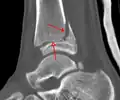

Une fracture triplane de la cheville vue par TDM

CT

Les tomodensitogrammes peuvent être indiqués en cas de risque de fracture fragmentée ou de fracture impliquant la surface articulaire[9]. Cette imagerie peut être utilisée pour la planification chirurgicale.